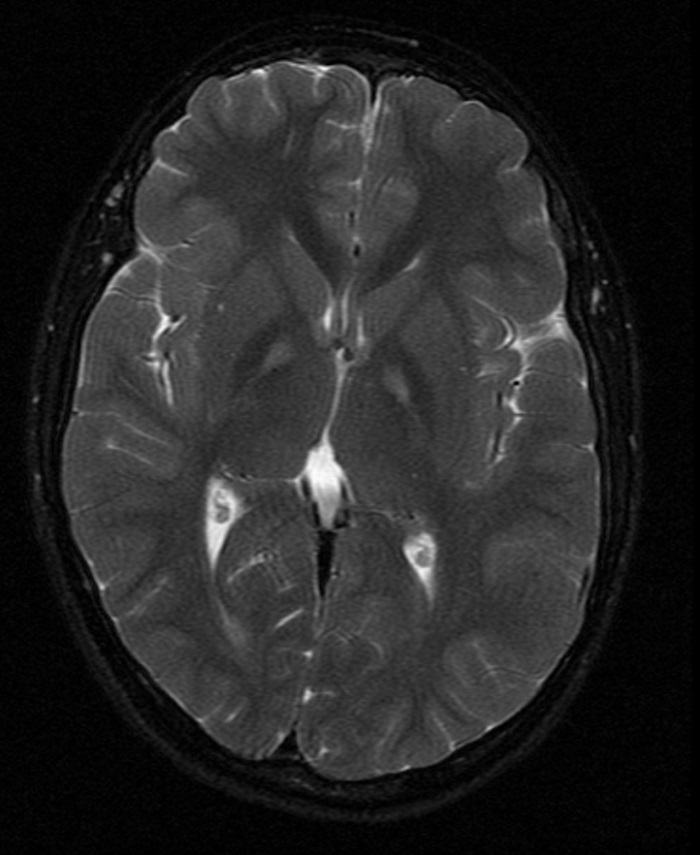

¿Qué observamos en el corte presentado de resonancia magnética cerebral?: